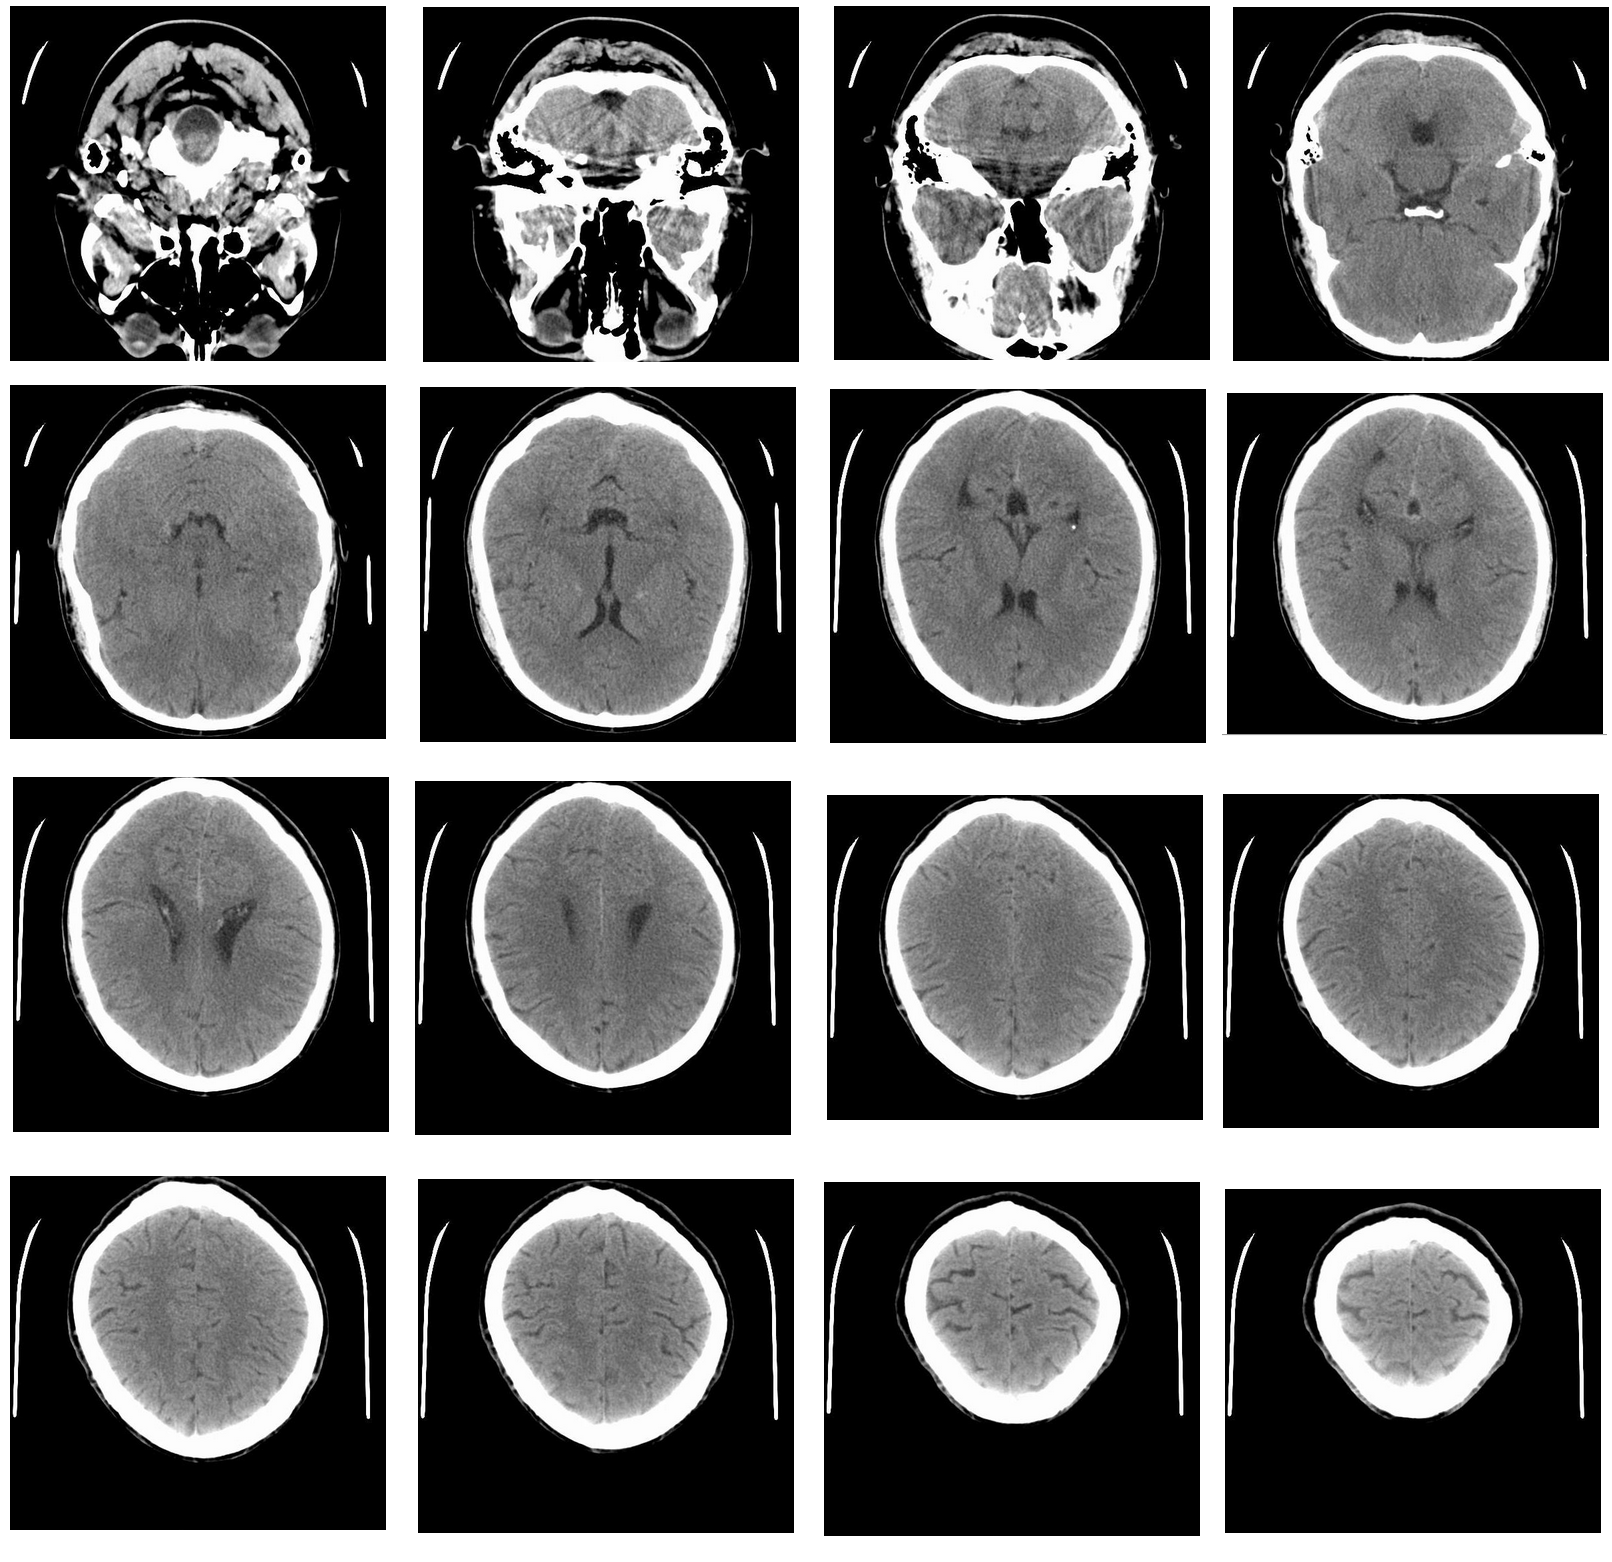

We conclude the section with numerical results presenting the electric and magnetic field over the human head data based on MRI scans. Our simulations are based on digital data with 29 two-dimensional slices, each one with 532 times 565 pixels. Each pixel’s intensity is a value from the range of [0, 255], and it’s proportional to the material’s (skull, skin, tissue, and air) normalized density. Exemplary slices of the human head from the MRI scan are presented in Figure 5. Next, according to the MRI scan data, we used the electromagnetic waves from the manufactured solution example, with material data changing on the skull, skin, tissue, and air. We assume air (MRI scan data 1), skin or brain (tissue in general) (1 approximation 240), and skull (approximation 240). We enforce different material data using the method described in this section. We summarize the results in Figure 6 for the electric waves, and Figure 7 for the magnetic waves.